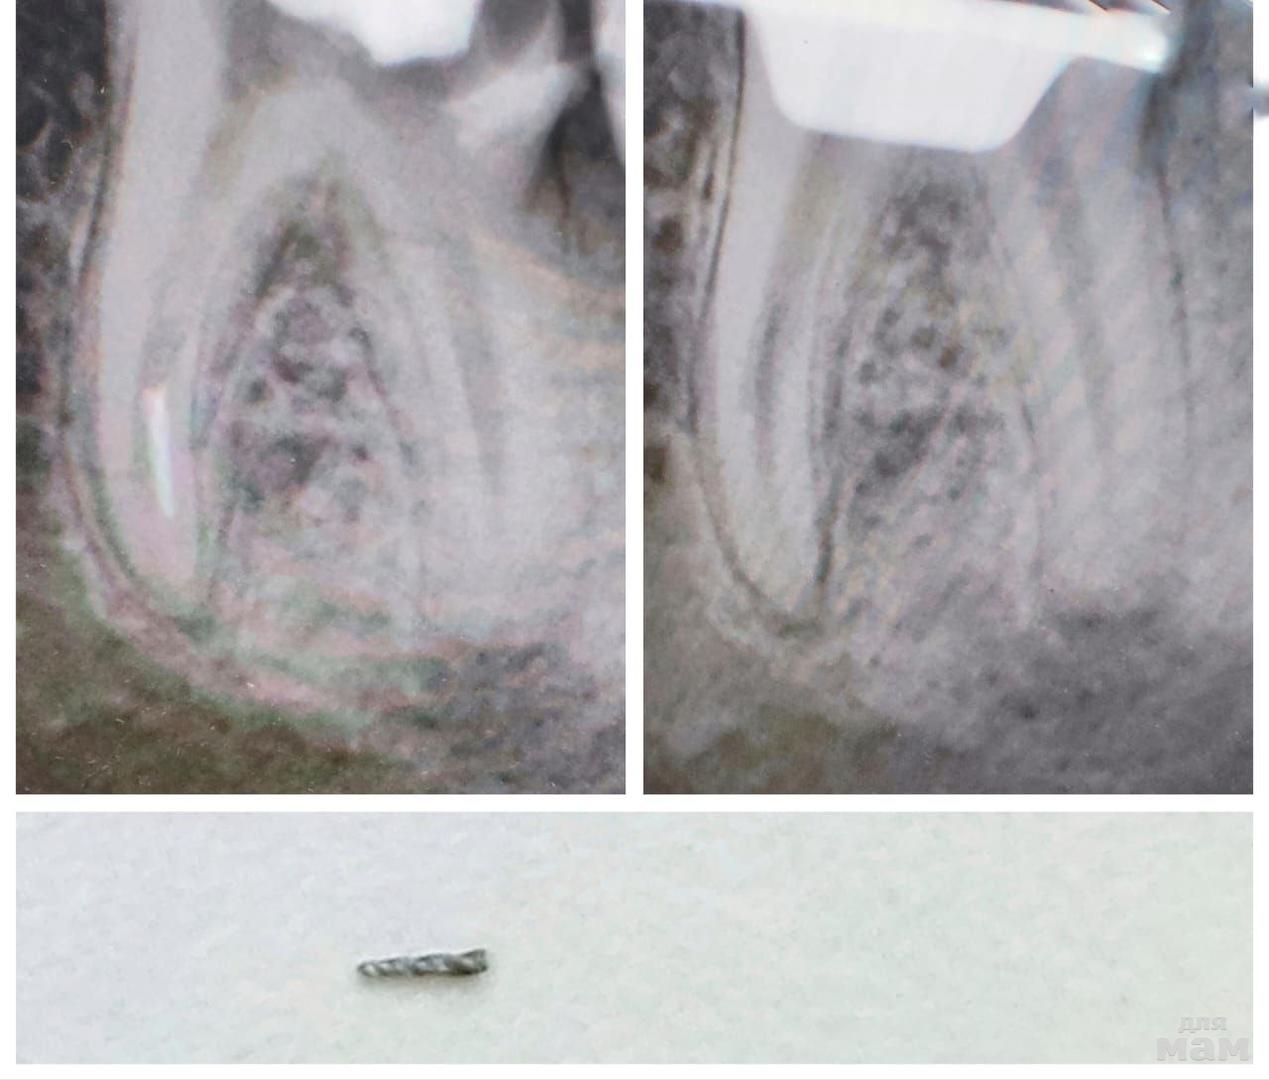

На снимке: в дальнем канале зуба четко виден застрявший кусочек инструмента. Вокруг корня – затемнение, типичное для хронического воспаления.

Что сделали: под анестезией открыли каналы в зубе. Расширили вход в канал специальными инструментами, и вот он – кончик сломанного инструмента! Доктор аккуратненько подцепила, потихоньку покрутила – и вытащила! Каналы промыла от души. Так как там воспаление, решили пока запломбировать каналы временной пастой с лекарством, чтобы все успокоилось. Потом я пошла на контрольный осмотр и окончательную пломбировку каналов. Полоскала рот антисептиком.